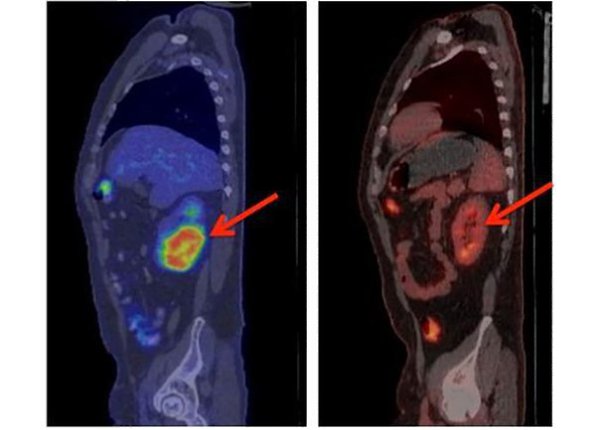

Через несколько недель у 27 из 29 пациентов с острым лимфобластным лейкозом анализ костного мозга показал полное отсутствие раковых клеток. 19 из 30 добровольцев с неходжкинской лимфомой полностью или частично излечились. У нескольких пациентов полностью рассосались опухоли килограммовой массы.